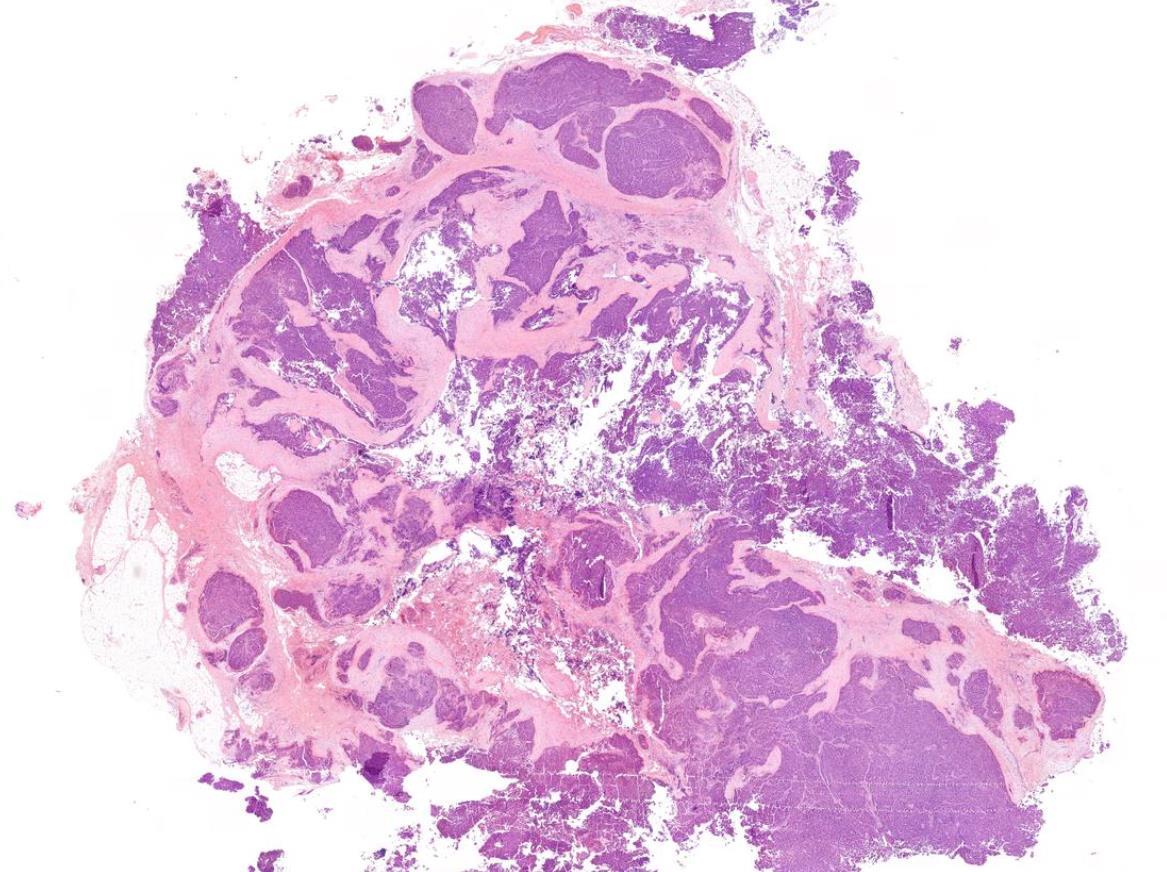

Case 10

Male 66 years, Compressive Goitre. 89g thyroid with ill-defined, yellowish haemorrhagic and fleshy nodule, 65mm..

PAX-8

TTF1

PTH

Case 10 Diagnosis

Metastatic clear cell renal cell carcinoma